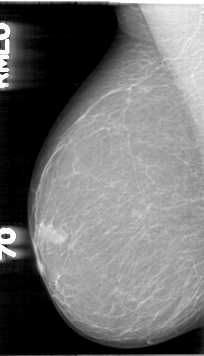

D_4003_1.RIGHT_MLO

RIGHT_MLO LINES 5326 PIXELS_PER_LINE 3046 BITS_PER_PIXEL 12 RESOLUTION 43.5 NON_OVERLAY